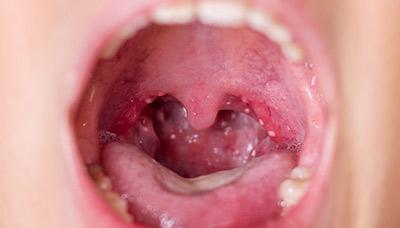

Вирус атакует клетки на небе, языке и связующих дужках, приводя к их отмиранию и образованию волдырей, заполненных экссудатом. При разрыве пузырьков возникают небольшие язвочки, которые могут болеть и, если активизируется бактериальная инфекция, нарываются. Обычно пузырьки лопаются и заживают в течение недели.

Инкубационный период герпесной ангины может длиться до 7 дней. Болезнь начинается остро: у пациента наблюдается снижение аппетита, общее недомогание и слабость, повышение температуры тела до фебрильных значений, болезненные ощущения в горле и увеличение лимфатических узлов, заложенность носа. При выраженной интоксикации могут проявляться симптомы со стороны желудочно-кишечной системы: тошнота, рвота и диарея. На слизистой оболочке ротоглотки появляются мелкие пузырьки, заполненные серозной жидкостью.

Вокруг пузырьков заметен воспаленный венчик, напоминающий проявления герпеса.

Через несколько дней пузырьки лопаются, и на их месте образуются эрозии, покрытые белым налетом. Эти эрозии почти не вызывают боли, но заживают медленно – до трех недель. На данном этапе болезни существует риск присоединения бактериальной инфекции, что потребует применения антибиотиков.

Специфические симптомы появляются позже: боль в горле, неудобства при глотании, воспалённые миндалины, а также пузырьки с гнойным содержимым (везикулы) на нёбе. На 1-2 день везикулы лопаются, образуя болезненные эрозии, которые затрудняют приём пищи и питьё.

При герпетической ангине в первые два дня на нёбе и миндалинах могут появляться мелкие пузырьки, заполненные мутной или белой жидкостью.

Следующий этап — осмотр глотки и пальпация шейных лимфоузлов. При герпесной ангине наблюдается покраснение глотки, наличием пузырьков с гнойным содержимым или язв, увеличены шейные и подчелюстные лимфоузлы.